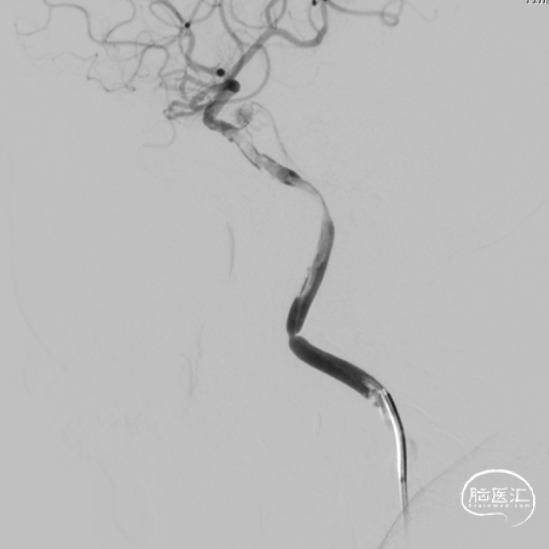

1. 术中造影检查。以改良Seldinger法穿刺右侧股动脉成功后,置8F动脉鞘,在泥鳅导丝引导下,和沃比Pilote™ 088导管同轴入路,带领Pilote™ 088导管顺利越过主动脉弓后,行主动脉弓造影及颅内造影,证实右侧劲内动脉段闭塞。

2. 颈动脉段抽吸取栓。反复尝试超选微导丝,穿过颈内动脉闭塞段已确认真腔。

通过微导丝和微导管的同轴通路搭建,顺利入路Esperance® 6F 125cm远端通路导管到达颈内动脉C1近端。与闭塞段置入2.5mm*15mm的冠脉球囊,对准闭塞部位以额定压由远及近扩张球囊。

撤出球囊后,造影见颈内动脉白色血栓影。

将Esperance® 6F 远端通路导管抵进颈动脉闭塞段,予以负压吸引,与闭塞段由远及近反复抽吸,见大负荷血栓吸出。

3. 颈内动脉段再次取栓。与颈内动脉C1末端置入并释放保护伞。

撤回Pilote™ 088导管及Esperance® 6F 远端通路导管至颈总动脉后造影示,颈内动脉端仍存在血栓影。

继续上高Pilote™ 088导管及Esperance® 6F 远端通路导管至颈内动脉近端,置入4.0mm*30mm球囊,对准闭塞处扩张后复查造影,见栓子堵于保护伞端。

通过Esperance® 6F 远端通路导管输送微导管到位,与闭塞段植入7mm*50mm颈动脉支架,定位准确后释放。支架释放后见血管扩张,前向血流进一步恢复。

回收保护伞后见造影示颈内动脉血流恢复。

10分钟后复查造影,见支架内血栓形成,大脑中动脉闭塞。

术后即刻颈总动脉造影示近远端前向血流恢复良好。